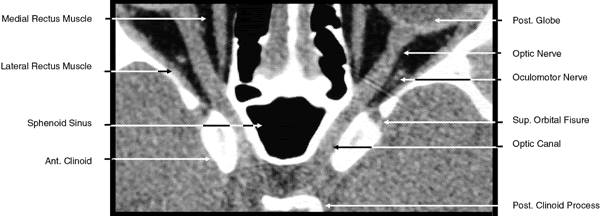

The globe is shown in Figure 12. The orbit and periorbital structures are shown in Figures 13 through 16, and the optic canal is shown in Figures 17 through 26. The cavernous sinus and optic chiasm are shown in Figures 27 and 28, and the posterior visual pathway and cranial nerves are shown in Figures 29 through 33.

Fig. 23. Axial images at the level of midorbit. A. Computed tomography scan. B. T1-weighted magnetic resonance imaging.